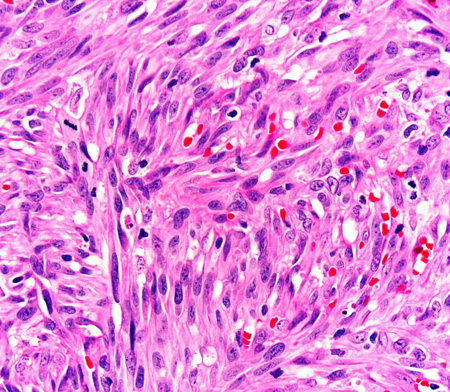

Biópsias por punch cutâneo são fáceis de serem realizadas e prontamente ajudam a descartar condições com sintomas semelhantes. A histopatologia revela células fusiformes atípicas características.[36]

Técnicas de imuno-histoquímica podem ser usadas para detectar os seguintes marcadores expressos por células lesionais do sarcoma de Kaposi: antígeno nuclear associado a latência-1 (LANA-1, um marcador substituto para HHV-8); CD31/CD34 (imunomarcadores de células endoteliais vasculares) e D2-40 (um imunomarcador de células linfáticas).[37][38]

Uma coloração positiva para LANA-1 pode estabelecer o diagnóstico de SK; o CD31 e o CD34 podem ser úteis se não estiver claro se o tumor tem origem vascular.[2][5][38]

[Figure caption and citation for the preceding image starts]: Fotomicrografia da histopatologia do sarcoma de Kaposi mostrando fascículos de células tumorais fusiformes vasoformadoras (coloração de hematoxilina e eosina)Do acervo do Dr. Liron Pantanowitz; usado com permissão [Citation ends].